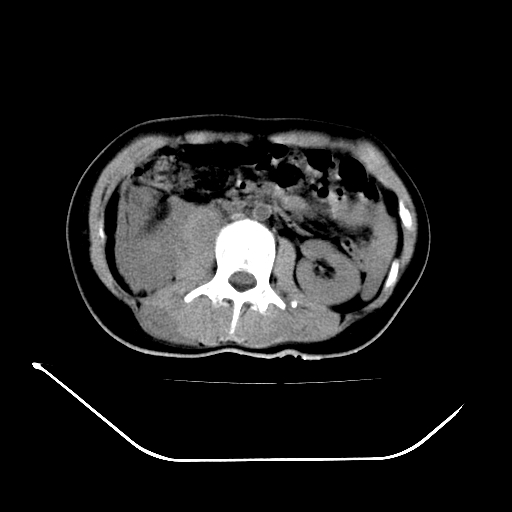

以下是引用liuyue在2008-7-19 13:02:00的发言:[br]1.肝右叶后下段及右肾挫裂伤伴腹腔积血。[br]2.右侧多发性肋骨骨折、横突骨折、右髂骨骨折伴周围软组织挫伤。[br]3.右侧腰大肌肿胀,并可见低密度影,如为气体,则肠道挫裂伤待除外。

以下是引用zhengfaming在2008-7-19 14:42:00的发言:[br]1.肝右叶后下段及右肾挫裂伤伴腹腔积血。脾脏挫裂伤待排[br]2.右侧多发性肋骨骨折、横突骨折、右髂骨骨折伴周围软组织挫伤。[br]3.右侧腰大肌肿胀,并可见低密度影,如为气体,则肠道挫裂伤待除外

以下是引用道哥在2008-7-19 16:52:00的发言:[br]肝右叶后下段及右肾挫裂伤、脾破裂伴腹腔积血。[br]2.双侧多发性肋骨骨折、横突骨折、右髂骨骨折伴周围软组织挫伤。[br]3.右侧腰大肌肿胀,并可见低密度影,如为气体,则肠道挫裂伤待除外。